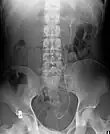

Ureteric stent

Example of a ureteral stent used to alleviate hydronephrosis of the kidney

Ureteral stents are used to ensure the patency of a ureter, which may be compromised, for example, by a kidney stone. This method is sometimes used as a temporary measure to prevent damage to a kidney caused by a kidney stone until a procedure to remove the stone can be performed.

An ureteral stent it is typically inserted using a cystoscope, and one or both ends of the stent may be coiled to prevent movement. Ureteral stents are used for various purposes, such as temporary measures to prevent damage to a blocked kidney until a stone removal procedure can be performed, providing drainage for compressed ureters caused by tumors, and preventing spasms and collapse of the ureter after trauma during procedures like stone removal. The thread attached to some stents may cause irritation but allows for easy removal by pulling gently. Stents without threads require cystoscopy for removal. Recent developments have introduced magnetic retrieval systems that eliminate the need for invasive procedures like cystoscopy when removing the stent. The use of magnets enables simple extraction without anesthesia and can be done by primary care physicians or nurses rather than urologists. This method has shown high success rates across different patient groups including adults, children, and kidney transplant patients while reducing costs associated with operating room procedures.